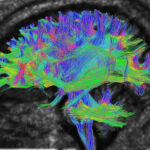

Are you seeking an affordable MRI Tractography? Medifyhome offers competitively priced MRI and CT scans, partnering with top NABL certified diagnostic centers and clinics. Our facilities ensure high quality imaging and accurate results. MRI tractography is a neuroimaging technique used to visualize and map the brain’s pathways of white matter tracts. It is based on diffusion MRI, which measures the movement of water molecules, revealing the orientation of neural fibers. This method is commonly applied to study brain connectivity, investigate neurological disorders, and guide surgical planning by identifying critical pathways. Tractography algorithms, such as deterministic and probabilistic approaches, reconstruct the trajectories of these fibers using mathematical models. While powerful, the technique has limitations, including distinguishing crossing fibers and accurately representing complex brain structures. To book an MRI Tractography scan appointment, visit our platform, Medifyhome, or contact us at +919100907036 or +919100907622 for reasonable prices.

An MRI tractography scan is a specialized imaging technique that uses magnetic resonance imaging (MRI) to visualize and map the brain’s white matter pathways. These pathways, made up of bundles of nerve fibers, are crucial for communication between different brain regions. Tractography relies on diffusion-weighted MRI, which measures the movement of water molecules within the tissue to infer the orientation of these fibers. The resulting images allow clinicians and researchers to assess brain connectivity, detect abnormalities, and plan surgeries that avoid critical brain structures. It is non-invasive and often used in the diagnosis and study of conditions like brain tumors, stroke, and neurodegenerative disorders.